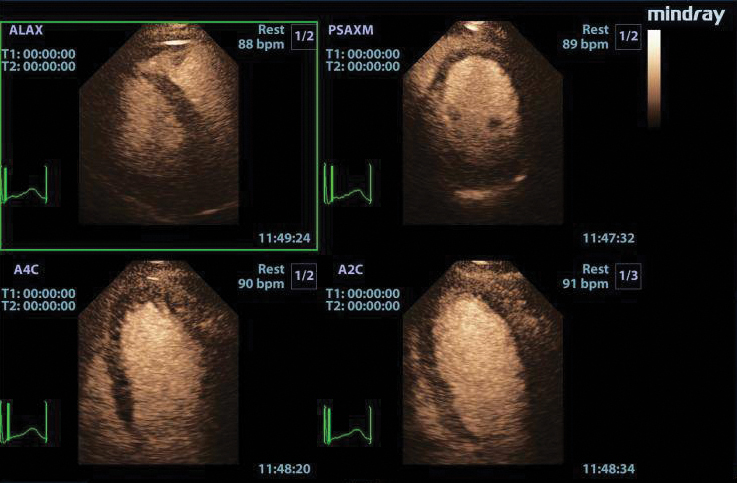

LVO with Stress Echocardiography

The combination of LVO during stress examinations enhances differentiation between tissue and the blood pool, providing better visualization of the endocardium. This package includes customizable user protocols, flexible wall motion scoring, and a comprehensive reporting suite.